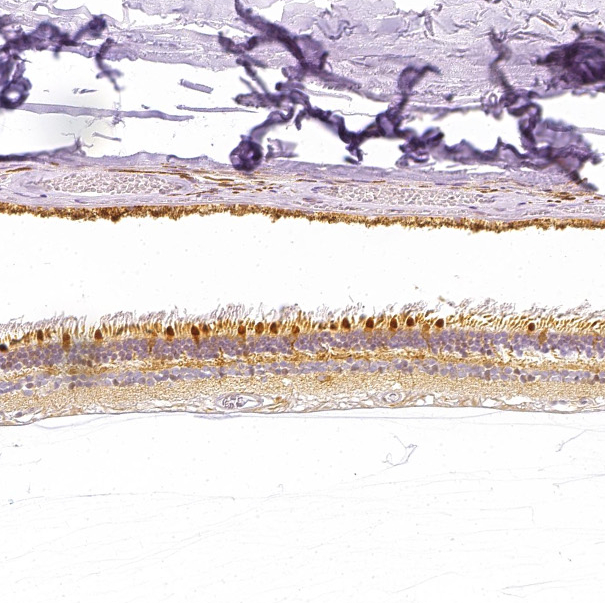

Immunohistochemical staining of human heart muscle shows moderate granular cytoplasmic positivity in cardiomyocytes.